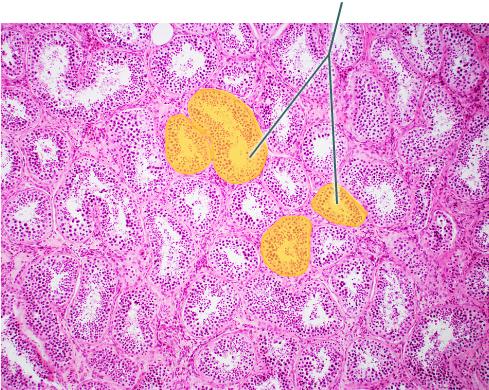

Identify the highlighted structure.

Seminiferous Tubules

What hormone is necessary for the highlighted structure to produce viable sperm?

FSH